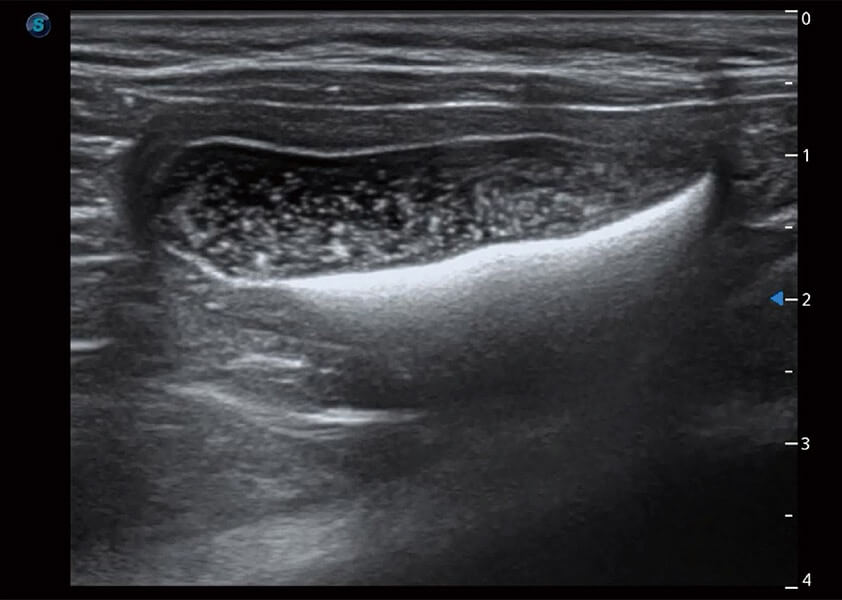

ProPet 60 作為一款高端臺(tái)式動(dòng)物超聲設(shè)備,為動(dòng)物醫(yī)生的日常診斷提供了一系列貼合動(dòng)物臨床需求、解決臨床實(shí)際問題的高級(jí)成像功能。憑借全系列高清探頭,滿足醫(yī)生對(duì)腹部、心臟、生殖、淺表、肌骨等成像的所有需求,切實(shí)幫助您提升檢查效率,提高診斷信心。